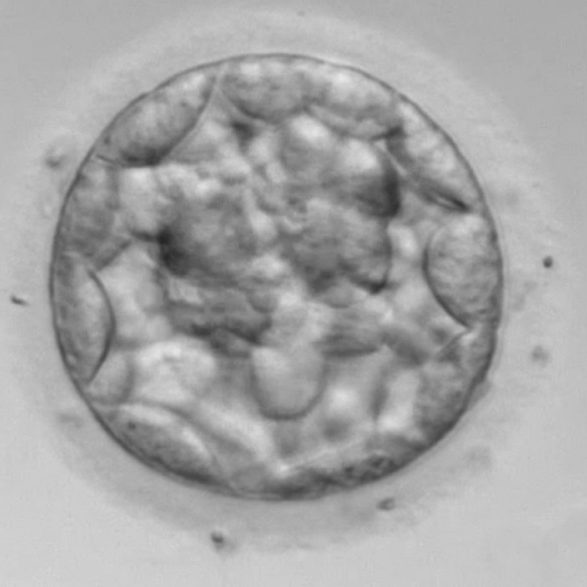

4.卵管内での受精卵の発育

5.着床